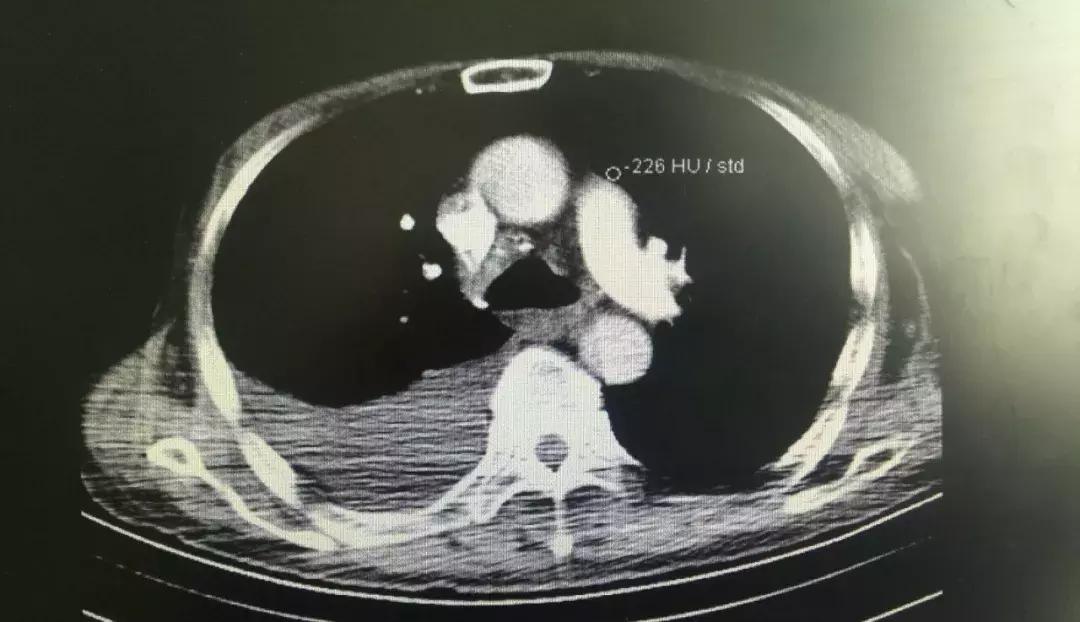

20多天前,70岁的保大爷出现了胸闷气急呼吸困难、胸痛难耐、咳嗽、日夜咯血的症状,甚至无法躺平休息。老伴见保大爷这么受罪,叫来子女一同把保大爷送往海西州人民医院,内科罗燕琴医生经过检查后发现血D二聚体明显升高,这意味着要警惕血栓性疾病,平扫CT显示右肺病变,但到底是肺出了什么问题引发这么严重的症状,还得进一步检查。

(保大爷平扫CT片子)

唐小平仔细阅读了肺部CT,不能完全排除肺栓塞。但在有肺部活动性出血的情况下,最保守的治疗方法只有垂体后叶素止血治疗,但保大爷对药物有明显的副作用表现,腹痛、腹泻让老人苦不堪言。

“除了肺栓塞外,会不会是肺炎链球菌感染引起的大叶性肺炎?”唐小平眉头一紧,这个疑问在唐小平里闪现,病人右肺大片渗出,有咯血存在,结合在浙大一院积攒的丰富临床经验,从常见的感染性疾病来讲,很有可能是肺炎链球菌感染引起的大叶性肺炎。而致病力强的肺炎链球菌感染,很容易并发胸腔积液,目前病人胸痛剧烈,可能是干性胸膜炎导致的胸痛,而这样的胸腔积液,很可能短时间剧烈增加,严重包裹,不易引流,会给治疗带来极大的困难。